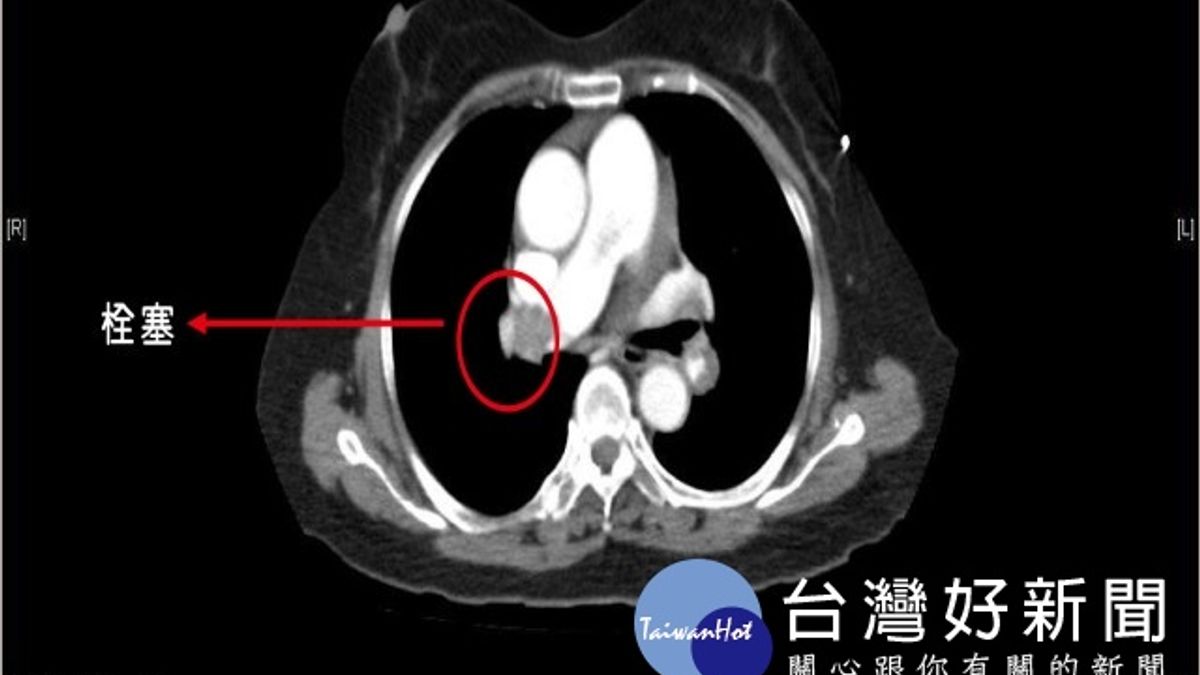

急診室醫師張勳昌從吳老血液報告中發現D-雙合蛋白(D-dimer)高出正常值10倍之多,強烈懷疑是急性肺栓塞,緊急安排胸部電腦斷層檢查,證實右邊的肺動脈有一大片血栓,緊急會診心臟內科醫師,緊急施藥治療後,轉往加護病房後續治療,各團隊合作挽回吳老一命,現健康出院,醫師仍持續追蹤中。